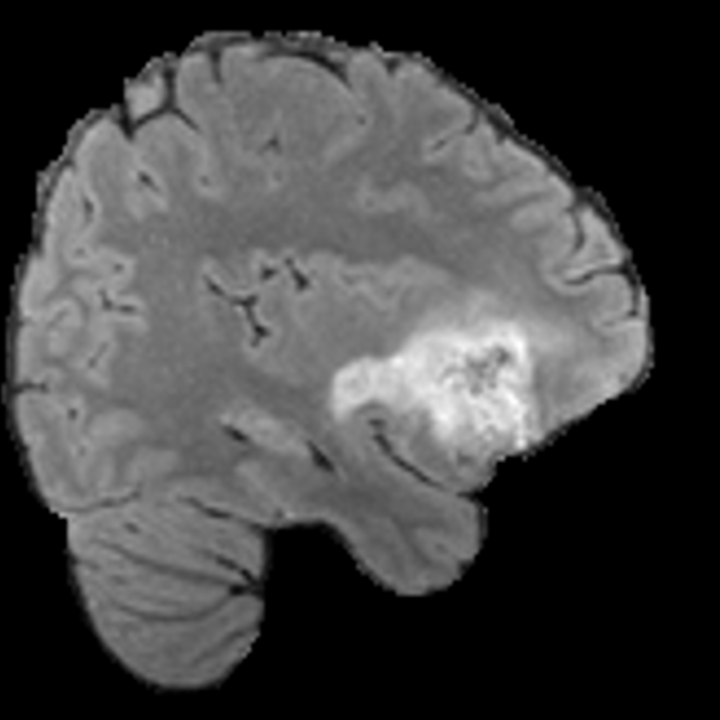

Our results unequivocally highlight the superior performance of X-Diffusion in terms of both qualitative and quantitative metrics. Representative MRI volumes generated by our pipeline, when juxtaposed with ground-truth images, showcased remarkable similarity, with even intricate physiological features like tumor information, spine curvature, and fat distribution being accurately captured.

Notably, X-Diffusion achieves sota dB for a few input slices while baselines require more than 60 input slices to achieve similar performance (Figure 7). The margin is more than 12 dB PSNR for the 1-slice input in both the BRATS and the UK Biobank benchmarks (see Table 1 and Figure 6). For reference, two randomly sampled MRIs from the UK Biobank would have a PSNR of 15.95 dB 0.36 (on 4800 randomly sampled examples). The slices from 3D reconstructed volumes at varying depths and axis of rotation visually match the ground truths (see Figures 5 and Figure 4). We also plot the error map (Figure 4) of such X-Diffusion generations to highlight the differences with the ground truth MRIs.

Preservation of Spine Curvature. For the spine segmentation on UK Biobank, we use a UNet++ model [81] with Dice Loss and use the curvature prediction of the spine followed in [9]). We measure the Pearson correlation factor [9] of spine curvature measured on the generated MRIs where the input is a single MRI coronal slice, or a single sagittal slice against the curvature of reference real MRIs of the same samples. The correlation coefficients are 0.89 for the coronal MRIs and 0.88 for the sagittal MRIs on the test set of 308 human-annotated angles.

B.3 Preservation of Spine Curvature and Fat

For the spine segmentation on UK Biobank, we use a UNet++ model [81] with Dice Loss. We use a model trained to predict curves on DXA on UK Biobank [9]. We show in Figure 20 that generated MRIs preserve the spine curvature from normal to severe scoliosis cases. We also study the case when DXA is used to generate the MRIs and show in Figure 14 how the correlation to real curvatures compares to the input MRI case. The curvatures of the MRI generated from the coronal plane match the DXA curvatures more than the curvatures generated from sagittal MRI. This is expected since the antero-posterior plane of DXA is equivalent to the coronal plane for MRIs. This also explains the greater Pearson’s correlation coefficient of the coronal MRI (0.89) and DXA-generated curvature (0.88) compared to sagittal-generated curvature (0.87) relative to the reference curvature on the coronal plane. We observe though that MRI generation using X-Diffusion from another plane than the conventional plane for scoliosis assessment is valid.